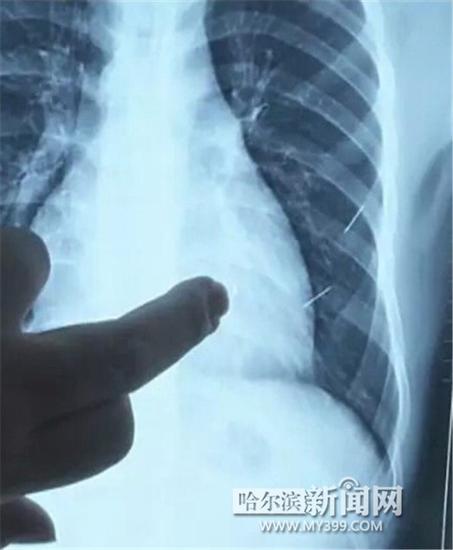

醫(yī)生指出X光片上的針狀物

昨日上午,記者在哈醫(yī)大二院第八住院部心外三病房找到了躺在病床上痛苦不堪的董立仁,家屬正在他身旁不斷安慰著他。見記者前來,董立仁母親李百燕拿出一張X光片,上面可以清晰地看到胸腔內(nèi)一共有4根針狀物,其中一根在心臟部位,兩根在胸腔壁上,還有一根在腹腔壁上。